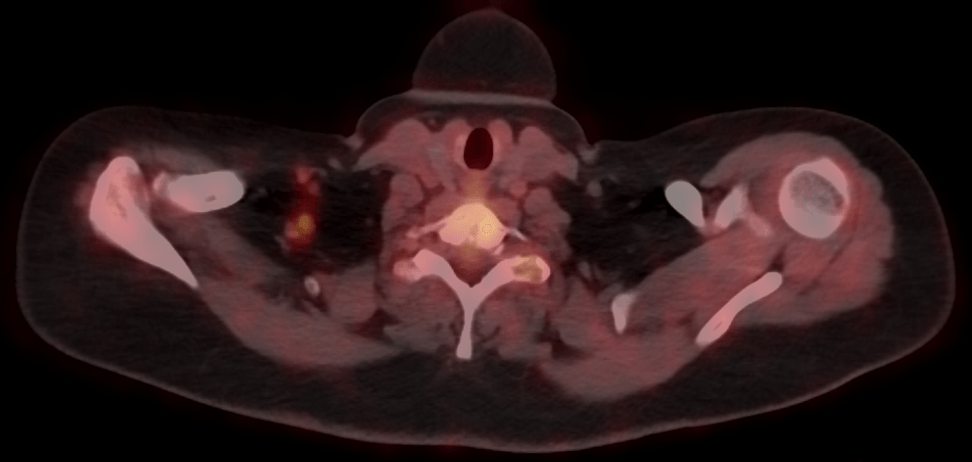

The evidence-based indications for use of PET-CT in the UK 2016 list four indications for FDG PET-CT in breast cancer:

- Assessment of multi-focal disease or suspected recurrence in patients with dense breasts.

- Assessment of extent of disease in selected patients with disseminated breast cancer before therapy.

- Assessment of response to chemotherapy in patients whose disease is not well demonstrated using other techniques: for example, bone metastases.